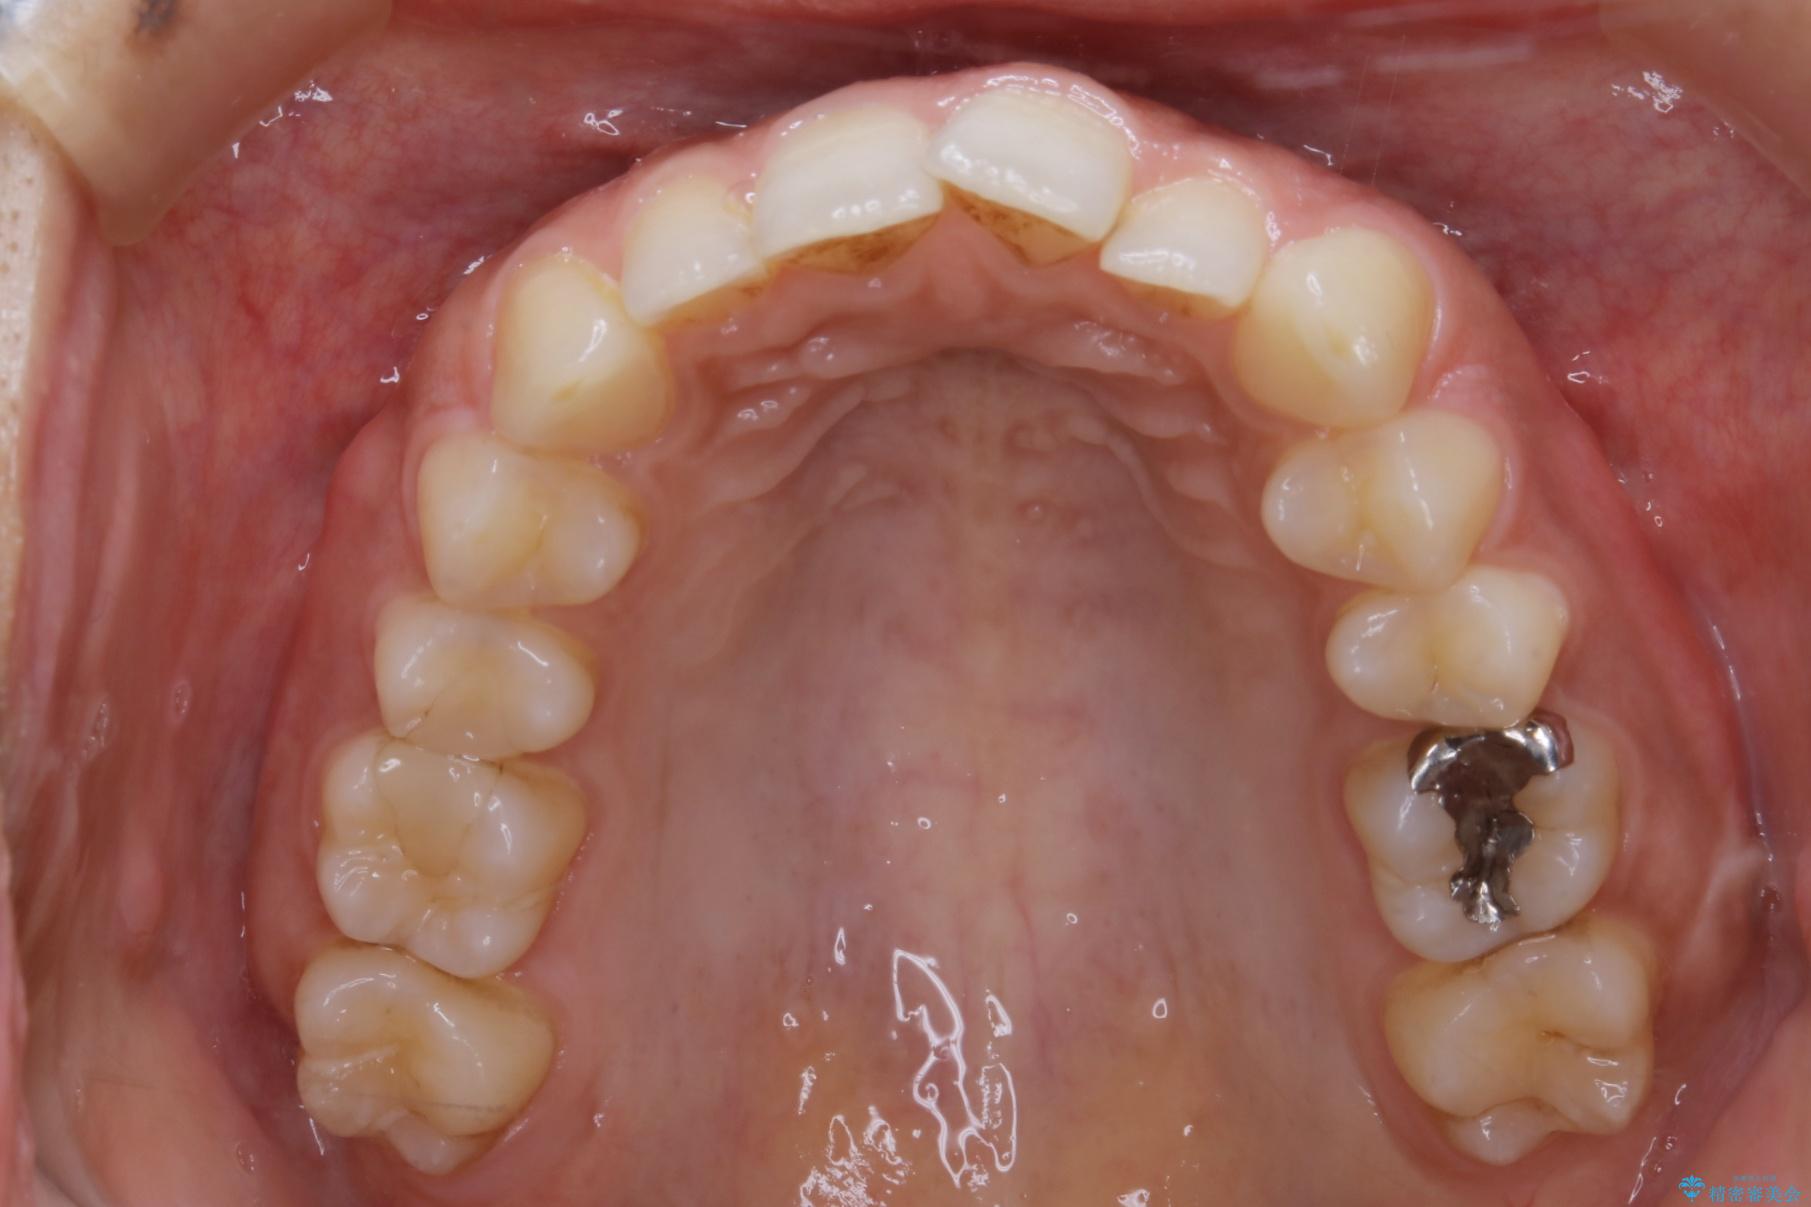

20代 女性 ゴムかけを併用し噛み合わせを改善!インビザライン矯正

気になるガタツキと噛み合わせを改善したいとご来院されました。

下の歯列よりも上の歯列が前に出ている状態を治すため、マウスピース矯正に加え、患者様にゴムかけのご協力をいただきました。その結果、ガタつきが改善し、上下の噛み合わせが適切な位置で合うようになりました。

歯列弓の拡大

歯並びが悪くなる原因の一つに「歯列弓の狭窄」というものがあります。

奥歯や前歯が内側(舌側)に倒れ込んでしまったり、歯が生えてくる位置が内側になってしまうことにより歯並びのアーチが狭くなってしまうことを言います。

このような場合、歯並びのアーチを拡大してあげるだけでもガタつきを無くすためのスペースがかなり作れることがあります。